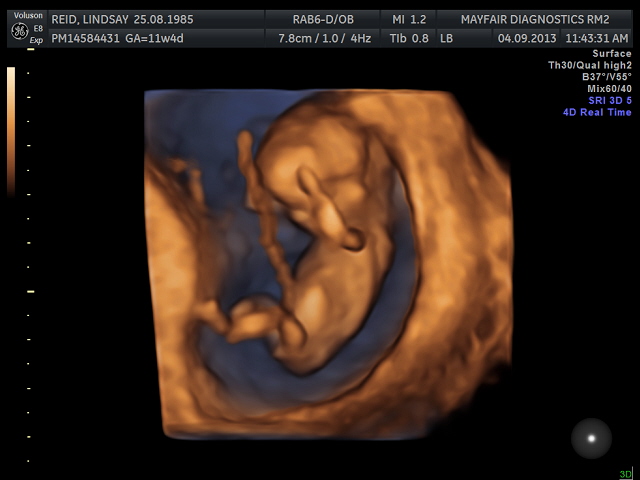

Had my 12 week scan today, I don't have any 2-d nub pics but I do have some 3-d ones! Based on the 3-d nubs and forehead/chin shape, I am guessing boy. :) Was hoping for a girl, but that's okay, lol. Heart rate was 166, baby was hyper and moving around so much!Attachment 13790Attachment 13791Attachment 13789